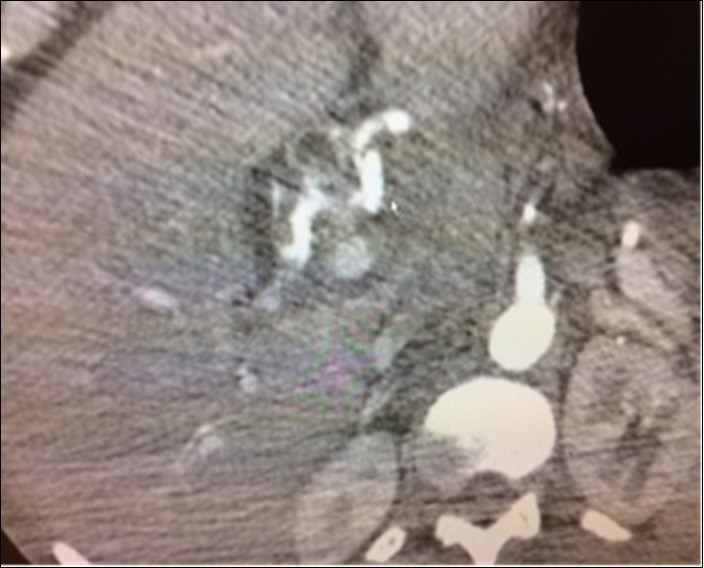

A 66 year old man was admitted to Christ Hospital in Jersey City, New Jersey, complaining of abdominal and back pain and weakness of at least one month duration. He had lost 40lbs of weight. Physical examination revealed mild mid abdominal tenderness and mental confusion. The temperature was 97.9. White blood count was 10.3 thousand per microliter. Computed tomography of the abdomen showed a 1.5 x 1.6 centimeter aneurysm of a branch of the superior mesenteric artery surrounded by some “inflammatory” reaction, Figure 3. Small stones were noted in the gall bladder. Immediate percutaneous embolization of the aneurysm was performed. CT scan of abdomen was “normal” before the present admission.

Figure 3.Case 3 – Superior Mesenteric Artery Branch Aneurysm surrounded by a halo.

In our second patient, Case 2, in addition to the aneurysm, the CT scan indicated “probable” bleeding, Figure 2, without any sign of systemic bleeding or infection, clinically or in the hemogram. The blood cultures were normal six days after treatment. White blood cell counts were normal and only mild anemia was present. Therefore, it is doubtful the aneurysm was mycotic. The “halo” around the aneurysm can be interpreted as pressure effect of the enlarging aneurysm on the surrounding tissues.

In one reported case, Wakana and colleagues found signs of systemic infection and “injected” mural thrombi in an ileocolic aneurysm calling the hallo effect as “dirty fat”, 7.